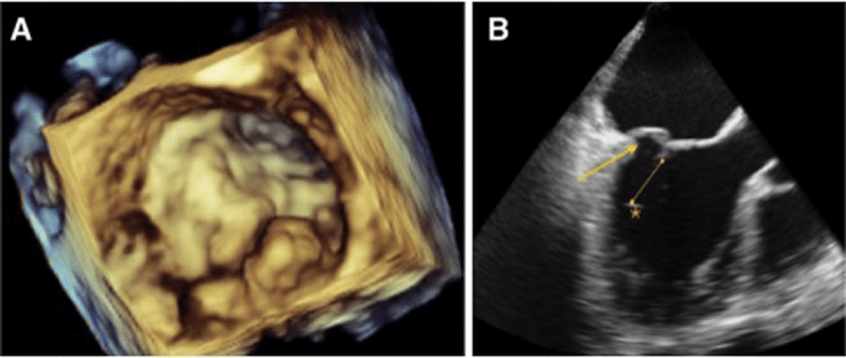

Echocardiography Sound wave or Ultrasound of heart to test heart pump and heart valves

2. Transesophageal echocardiogram (TEE): In this type of echocardiogram, the transducer is attached to the end of a flexible tube (probe) that is passed through the esophagus. This allows for more detailed images of the heart since the esophagus is located directly behind the heart.

3. We have advanced echo tools such as 3D-Echo imaging and Strain imaging